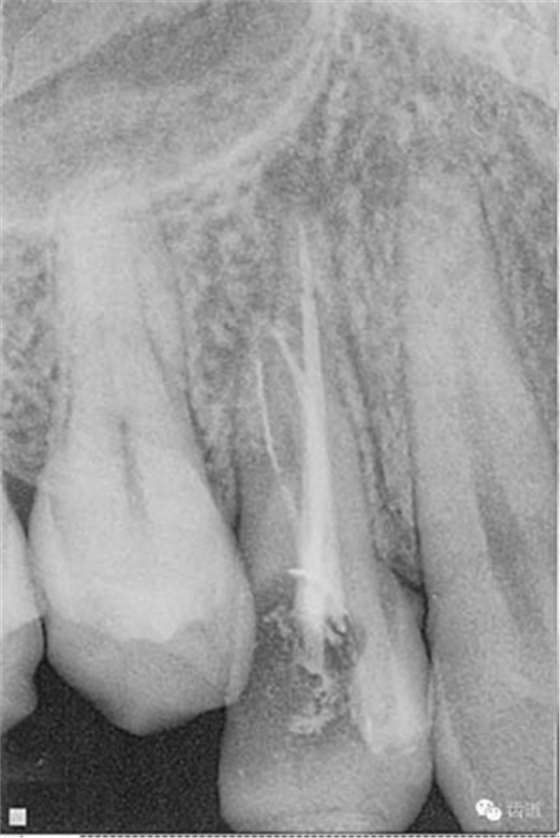

處理:顯微根管治療。放置橡皮障,去除暫封,顯微鏡下超聲去除頰側(cè)根管上段部分牙本質(zhì),探及遠(yuǎn)中根管口,見(jiàn)有糊劑遮蓋。Pathfile根管疏通,MTwo根管預(yù)備至2506#,配合3%次氯酸鈉和17%EDTA超聲蕩洗,干燥根管,放置氫氧化鈣糊劑,zoe暫封。

處理:放置橡皮障,去除暫封,超聲結(jié)合2%CHX清除遠(yuǎn)頰根管內(nèi)氫氧化鈣糊劑,主牙膠試合后95%酒精沖洗干燥根管,結(jié)合AHPlus糊劑連續(xù)波熱牙膠垂直加壓充填根管,樹(shù)脂分層粘接修復(fù)牙體。建議定時(shí)復(fù)診進(jìn)行嵌體修復(fù),患者未執(zhí)行。